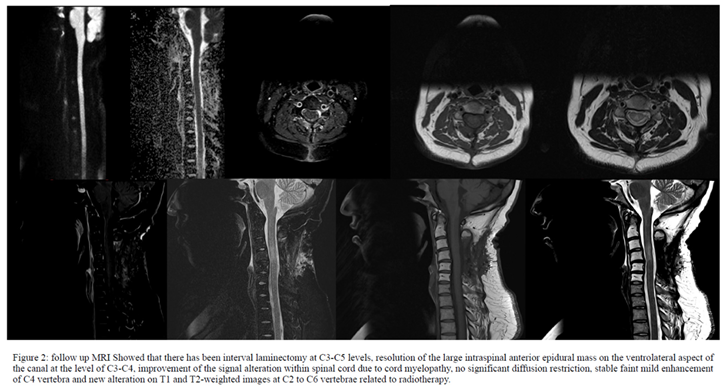

At the beginning of February 2020, the patient underwent anterior decompression and lesion resection at C3-4 and C5 laminectomy. A large panel of immunohistochemical stains were done on the pathologic sample and it showed that the tumor cells are strongly positive for TdT, CD99, CD79A, PAX5, CD43 and CD10, CD45, FLI1, CD20, CD3 and CD34. The stains for synaptophysin, NSE, WT1, myogenin, MPO, CD2, CD5, CD8 and CD1A are all negative. The proliferation marker Ki67 was positive in 70% of tumor cells, while PAS stain is negative. See Figure 2.

The patient was then commenced on United Kingdom acute lymphoblastic leukemia 14 protocol (UKALL14) on June 2020. On July 8th, 2020 a follow up MRI of the cervical spine was done after completion of induction chemotherapy and showed a significant improvement and resolution of anterior intraspinal epidural mass at the level of C3 and C4 vertebral bodies.